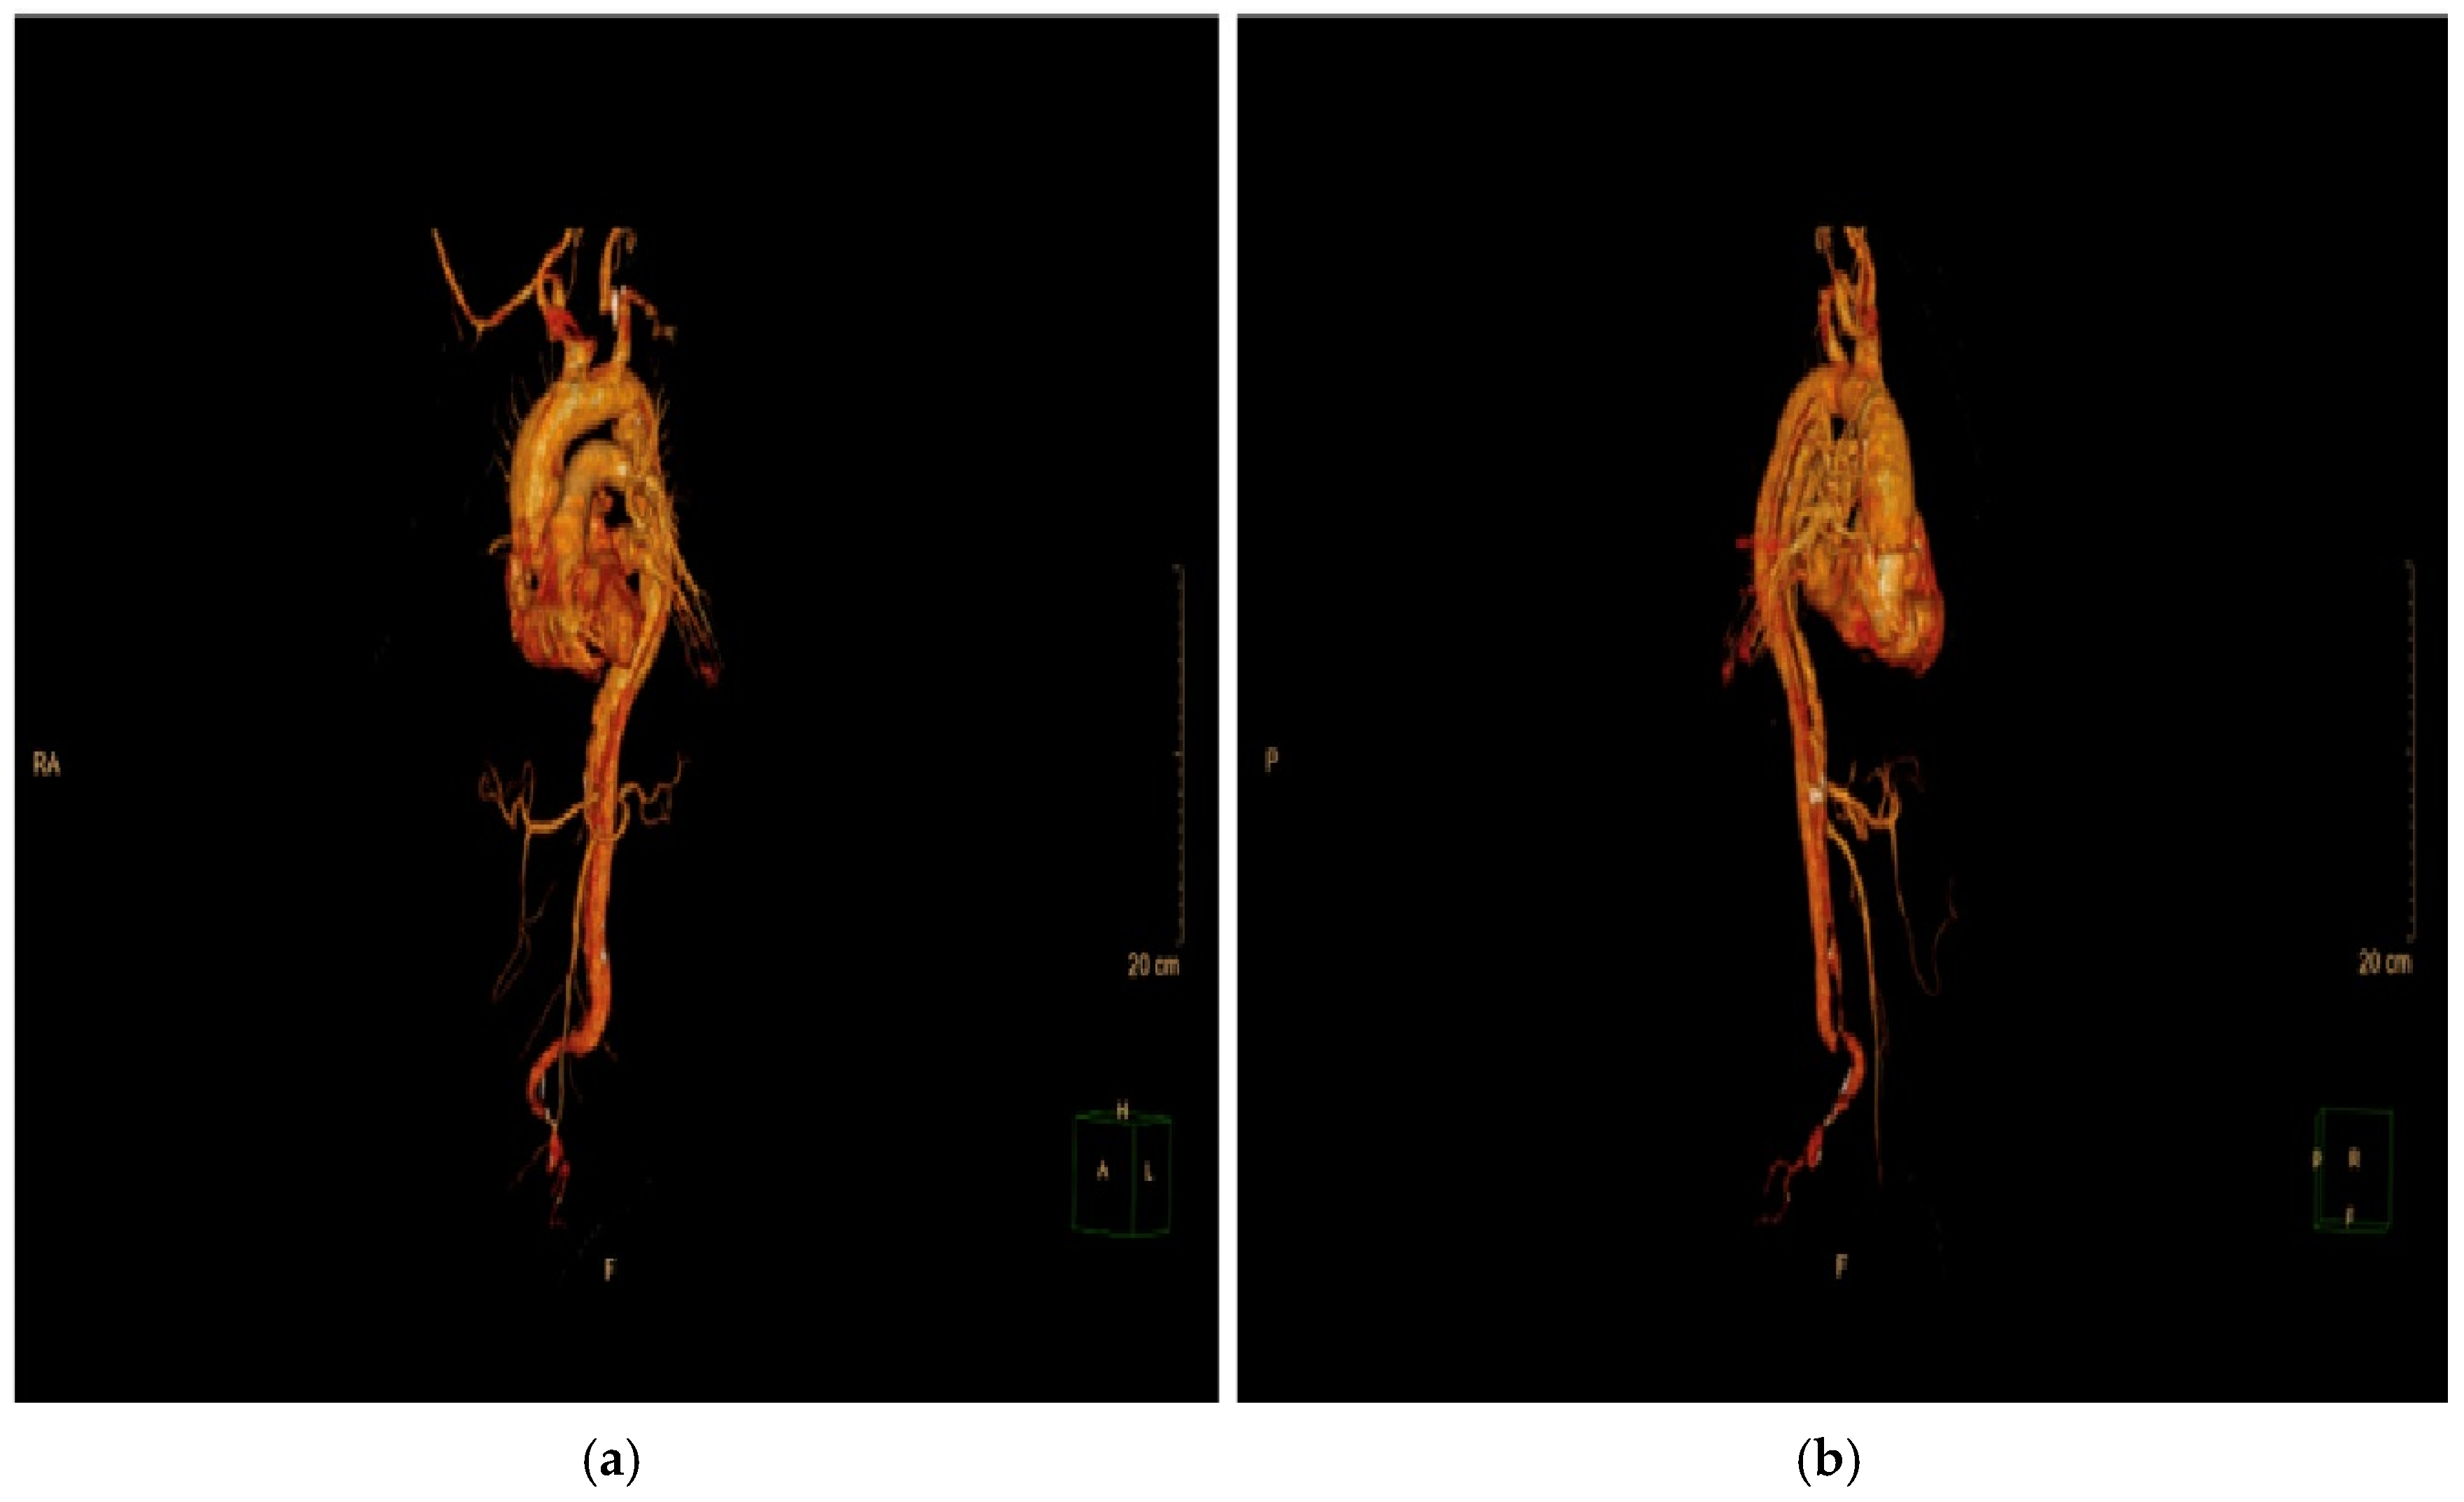

Imaging modalities, especially CTA, were essential for diagnostic and anatomical assessment. In our cohort, CTA findings directly influenced the management pathway in multiple instances. For example, in four cases (15.4%), pericardial effusion detected on imaging necessitated immediate surgical intervention to prevent cardiac tamponade. In nine patients (34.6%), extensive aortic arch involvement observed on CTA dictated the need for total arch replacement. Additionally, imaging findings identified branch vessel involvement in six patients (23.1%), which prompted closer intraoperative vascular assessment to prevent ischemic complications. These findings demonstrate that imaging was not merely a diagnostic tool but also a cornerstone in therapeutic decision-making, shaping both the urgency and extent of surgical intervention. This was exemplified by a representative case of a 57-year-old male with a complex DeBakey Type I dissection (Figure 9 and Figure 10). The case underscores the critical role of advanced imaging in identifying the extent of dissection and guiding timely surgical intervention, which is consistent with our study findings. The detection of aortic regurgitation in 26.9% and pericardial effusion in 19.2% underscores the efficacy of multimodal imaging in identifying problems that require immediate surgical intervention. Outcomes of surgical versus conservative management in our sample reflect findings from IRAD and other registries, revealing in-hospital mortality rates of 12.5% for surgically treated patients compared to 60.0% for those receiving conservative management. The decision between surgical and conservative management was primarily driven by patient stability, comorbidities, and imaging findings. Hemodynamic instability, evidence of rupture, and significant pericardial effusion were immediate surgical indications observed in 61.5% of our cohort. Conversely, conservative management was chosen in patients with advanced age, significant comorbidities, or family refusal of surgical intervention. Despite efforts to stabilize conservatively managed patients with pharmacological blood pressure control and vigilant monitoring, outcomes remained significantly inferior, highlighting the limitations of non-surgical approaches in Stanford Type A dissections. Kaplan–Meier survival studies indicated an 87.5% one-year survival rate for surgical cases against 30% for conservative care, highlighting the critical life-saving effect of prompt surgical intervention [20,21].

Figure 9. CT imaging of Stanford Type A aortic dissection: true and false lumen analysis—sagittal views: The sagittal images highlight an extensive dissection flap extending from the ascending aorta through the aortic arch and into the descending thoracic and abdominal aorta. The false lumen is clearly visible, with signs of thrombosis involving both the right and left common iliac arteries. These findings indicated a high risk of malperfusion and were pivotal in the decision to proceed with emergency surgical intervention, including ascending aortic replacement and aortic arch repair.